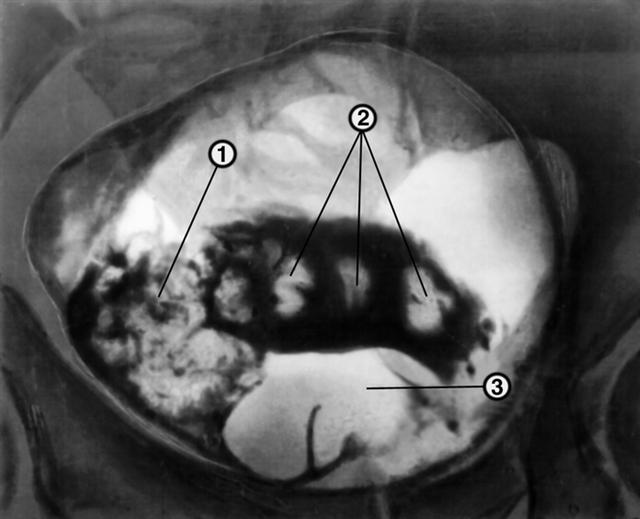

Рис. 2. Лакунарная цистограмма больного с аденомой предстательной железы, папиллярной опухолью и камнями мочевого пузыря: 1 — папиллярная опухоль мочевого пузыря; 2 — камни мочевого пузыря; 3 — аденома предстательной железы.